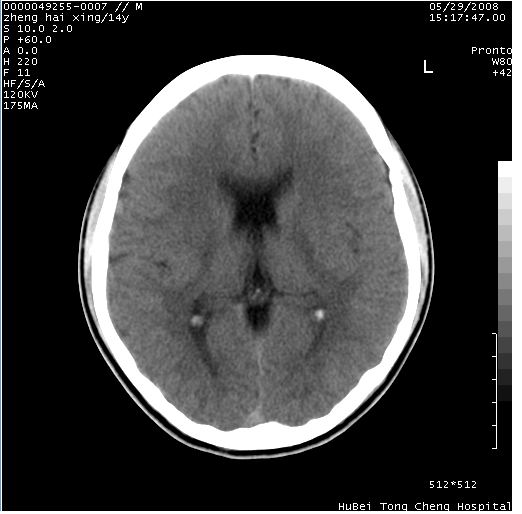

颅脑ct轴位平扫(层厚、层距均为10mm),图像如下:

双侧侧脑室之间无透明隔,双侧额角前方变扁,交角变钝。支持透明隔缺如!

透明隔缺如可为先天性缺如,亦可继发于因脑积水,脑室内压力增高,使其变薄,以至不能显示。一般无临床意义,但可并发于其他畸形或作为隔—视综合征的组成部分。

(隔—视发育不良综合征包括:1)原发性视神经发育不良,2)透明隔缺如,3)垂体功能不全,特别是生长激素不足或缺乏)